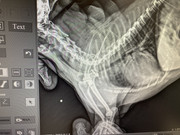

Коллапс трахеи форум

Коллапс трахеи форум 116 фотографий